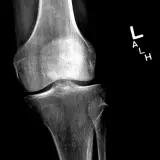

Over 2,100 interactive radiology cases, curated by radiologists for your level of training. Scroll, window, and view cases full screen โ€” just like on PACS. Click linked findings in each writeup to jump straight to them on the image. Cases include sample reports, a focused discussion section, original illustrations, and videos.

Casi completamente interattivi con gli strumenti che ti aspetti su un PACS: scroll, windowing, zoom, pan, misurazioni, ROI e modalitร  a schermo intero.

Annotazioni dettagliate evidenziano i reperti chiave direttamente sui casi. Clicca sui reperti collegati nella descrizione del caso per saltare alla loro esatta posizione sullo scan.